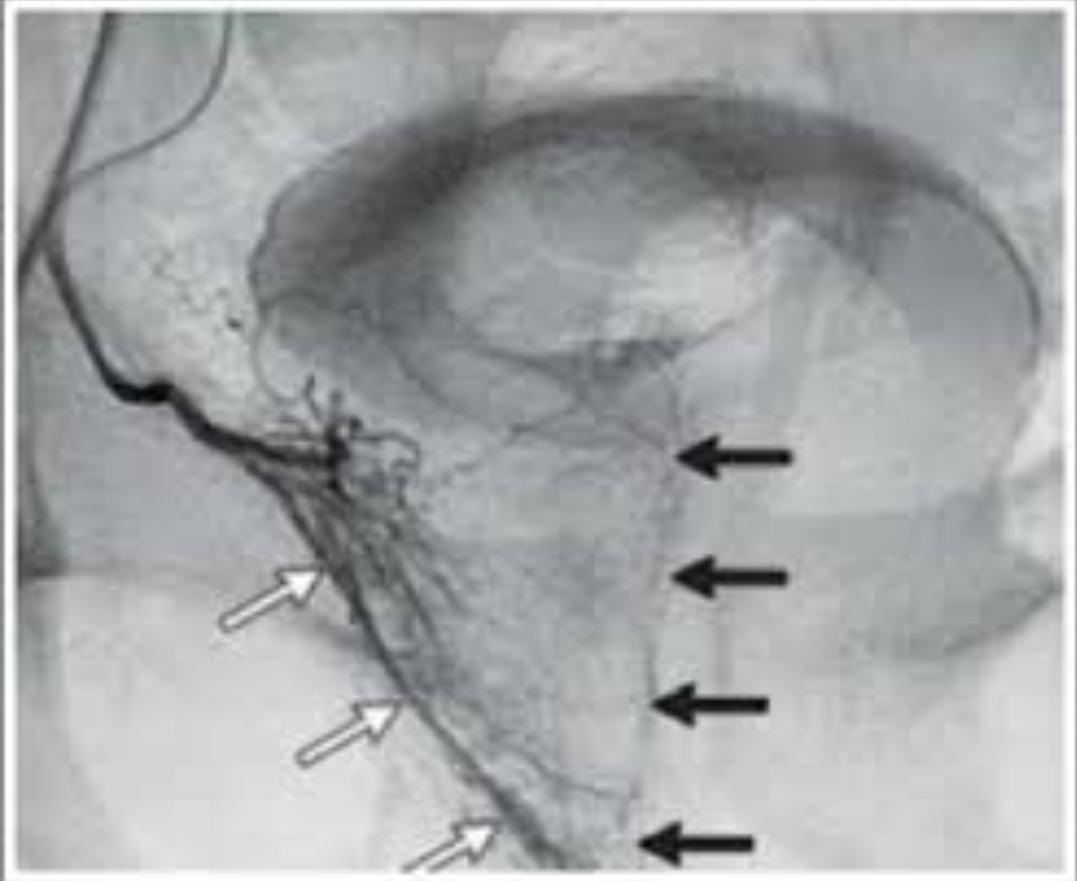

2. 전립선동맥색전술(Prostatic artery embolization)

대퇴동맥 또는 요골동맥을 통해 전립선 동맥을 색전하는 중재적 시술입니다. 비교적 고령, 수술 고위험군에서 선택됩니다. 전신마취가 필요 없다는 장점이 있습니다. 그러나 증상 개선 정도는 경요도 수술보다 다소 약하고, 3에서 5년 재시술률은 10에서 20퍼센트 이상으로 보고됩니다. 색전 비표적 합병증, 혈종, 드물게 감염이 가능합니다. 패혈증은 매우 드물지만 보고 자체가 전혀 없는 것은 아닙니다. (혈관을 말려죽인다고 생각하시면 됩니다.)